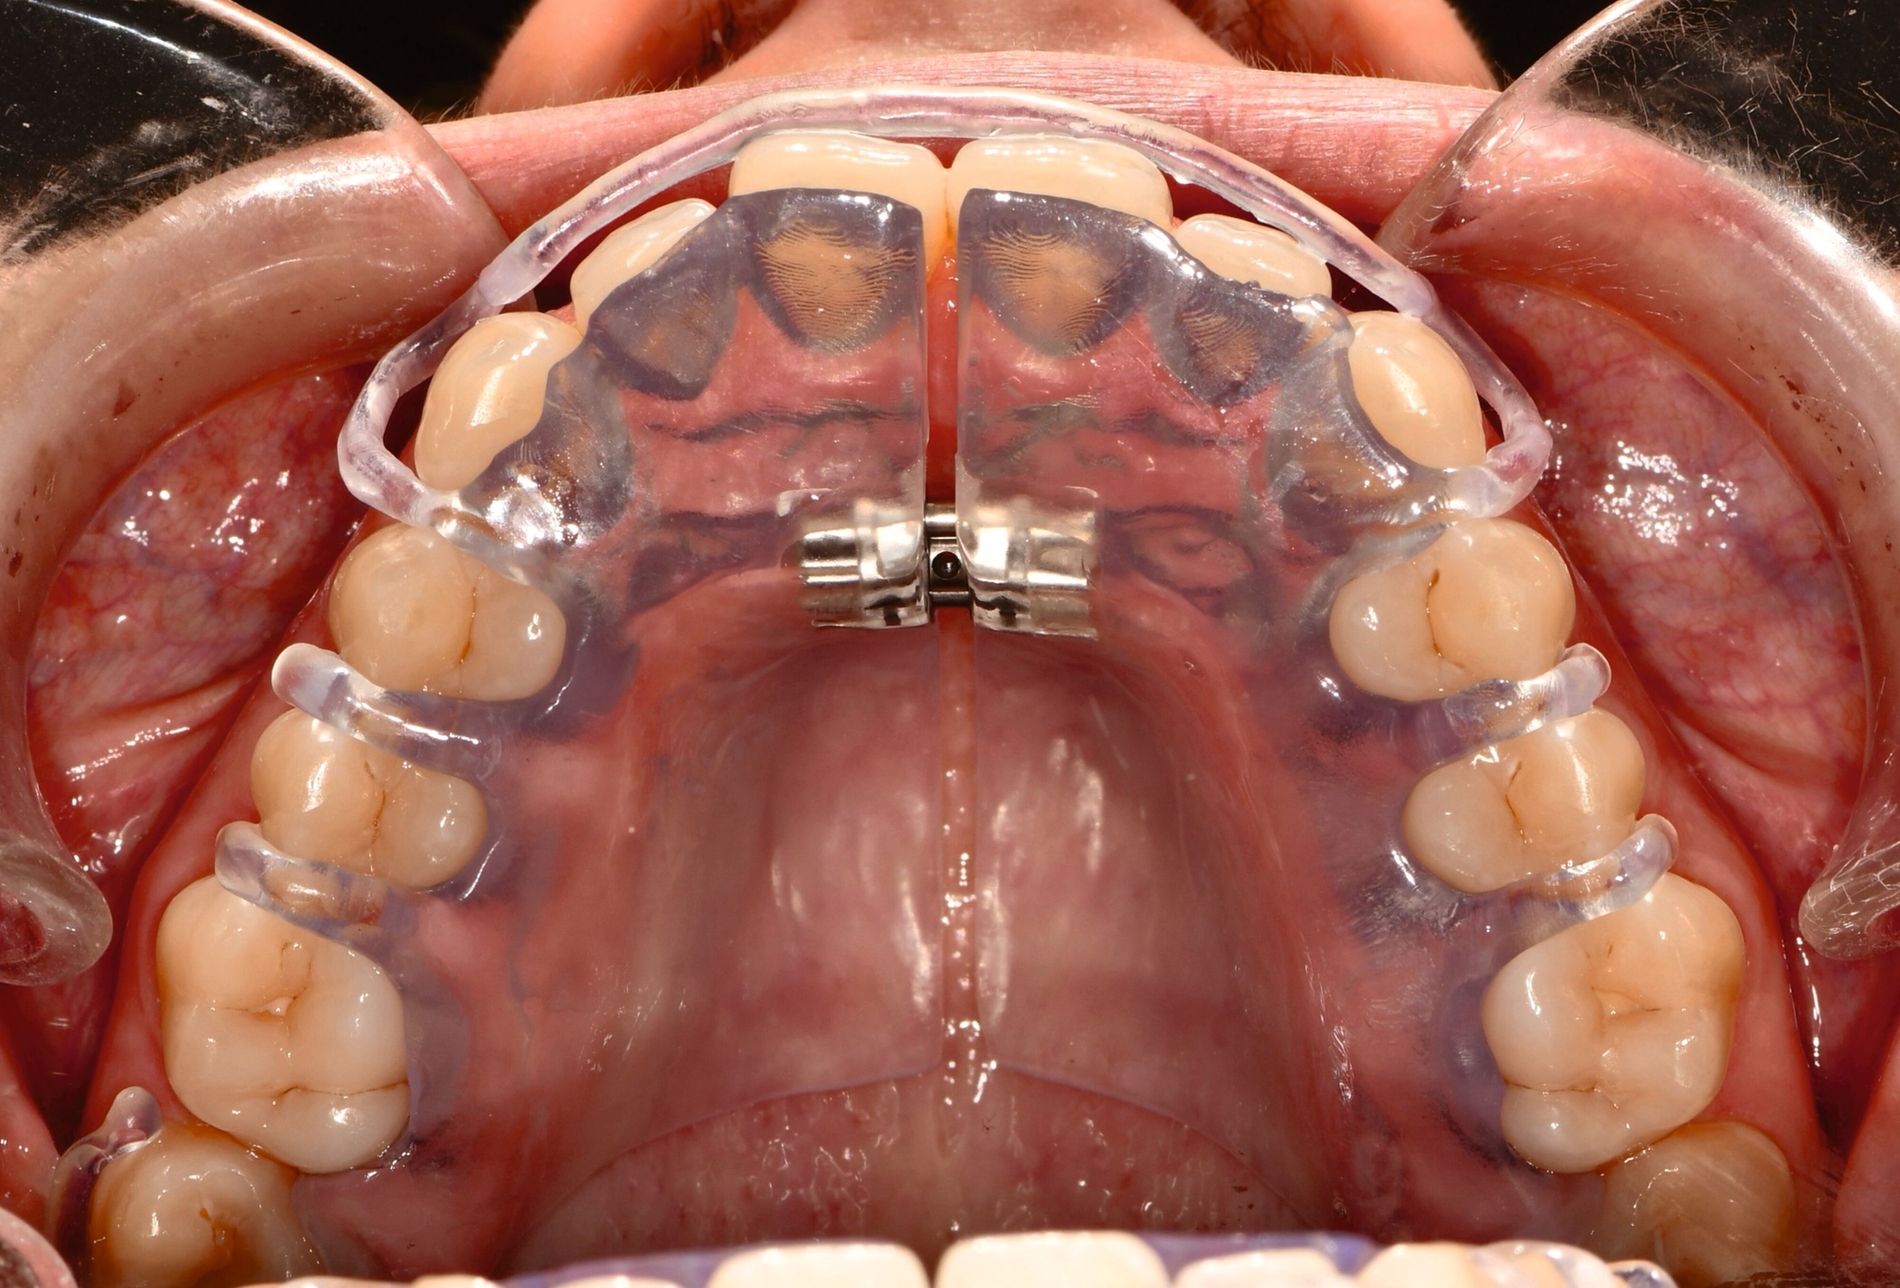

Herausnehmbare Apparaturen

Als hochinnovatives Feld hat sich auch die Herstellung herausnehmbarer Apparaturen im 3-D-Druck entwickelt (Abbildung 4), beschränkt sich jedoch noch auf einzelne Forschungsansätze [Al Mortadi et al., 2012; van der Meer et al., 2016; Graf et al., 2022; Keller et al., 2022]. Intensiv an neuen Konzepten in der Herstellung 3-D-gedruckter herausnehmbarer Apparaturen wird am Universitätsklinikum Heidelberg geforscht. Da herausnehmbare kieferorthopädische Apparaturen im Regelfall bei jungen Patienten eingesetzt werden, kommt dem Vorteil einer unbegrenzten Replikation und einer kostengünstigen und schnelleren Herstellung ein besonderer Stellenwert zu.

Im Unterschied zu konventionellen Apparaturen bestehen die 3-D-gedruckten Apparaturen vollkommen aus Kunststoff. Eine Einarbeitung metallischer Elemente nach dem 3-D-Druck ist möglich [Al Mortadi et al., 2012; Al Mortadi et al., 2024], erfordert jedoch zusätzlichen Zeitaufwand. Zur Herstellung herausnehmbarer Apparaturen eignen sich konventionelle praxisinterne 3-D-Stereolithografie-Drucker, die in vielen Fällen bereits im regulären Praxisalltag zum Modelldruck verwendet werden. Die verwendeten Kunststoffe sollten dabei eine Klasse-IIa-Zertifizierung aufweisen, so dass ein sicherer langfristiger intraoraler Einsatz der Apparatur gewährleistet ist. Weiter muss die Apparatur nach dem 3-D-Druck gemäß den Herstellerangaben nachprozessiert werden. Im Regelfall beinhaltet dieser Prozess ein Waschen in Isopropylalkohol (IPA) sowie eine Nachhärtung im Lichthärtegerät. Eigens durchgeführte Studien sowie die bisherige klinische Erfahrung bestätigen eine hohe mechanische Stabilität, eine hohe Passgenauigkeit sowie eine breite Akzeptanz der Patienten [Roser et al., 2021; Roser et al., 2023; Segnini et al., 2023]. Des Weiteren wecken die 3-D-gedruckten Apparaturen bei den meist jungen Patienten großes Interesse, was wiederum die Trage-Compliance unterstützt. Durch weitere Entwicklungen im 3-D-Druckbereich wird zukünftig auch ein Farbdruck möglich werden.